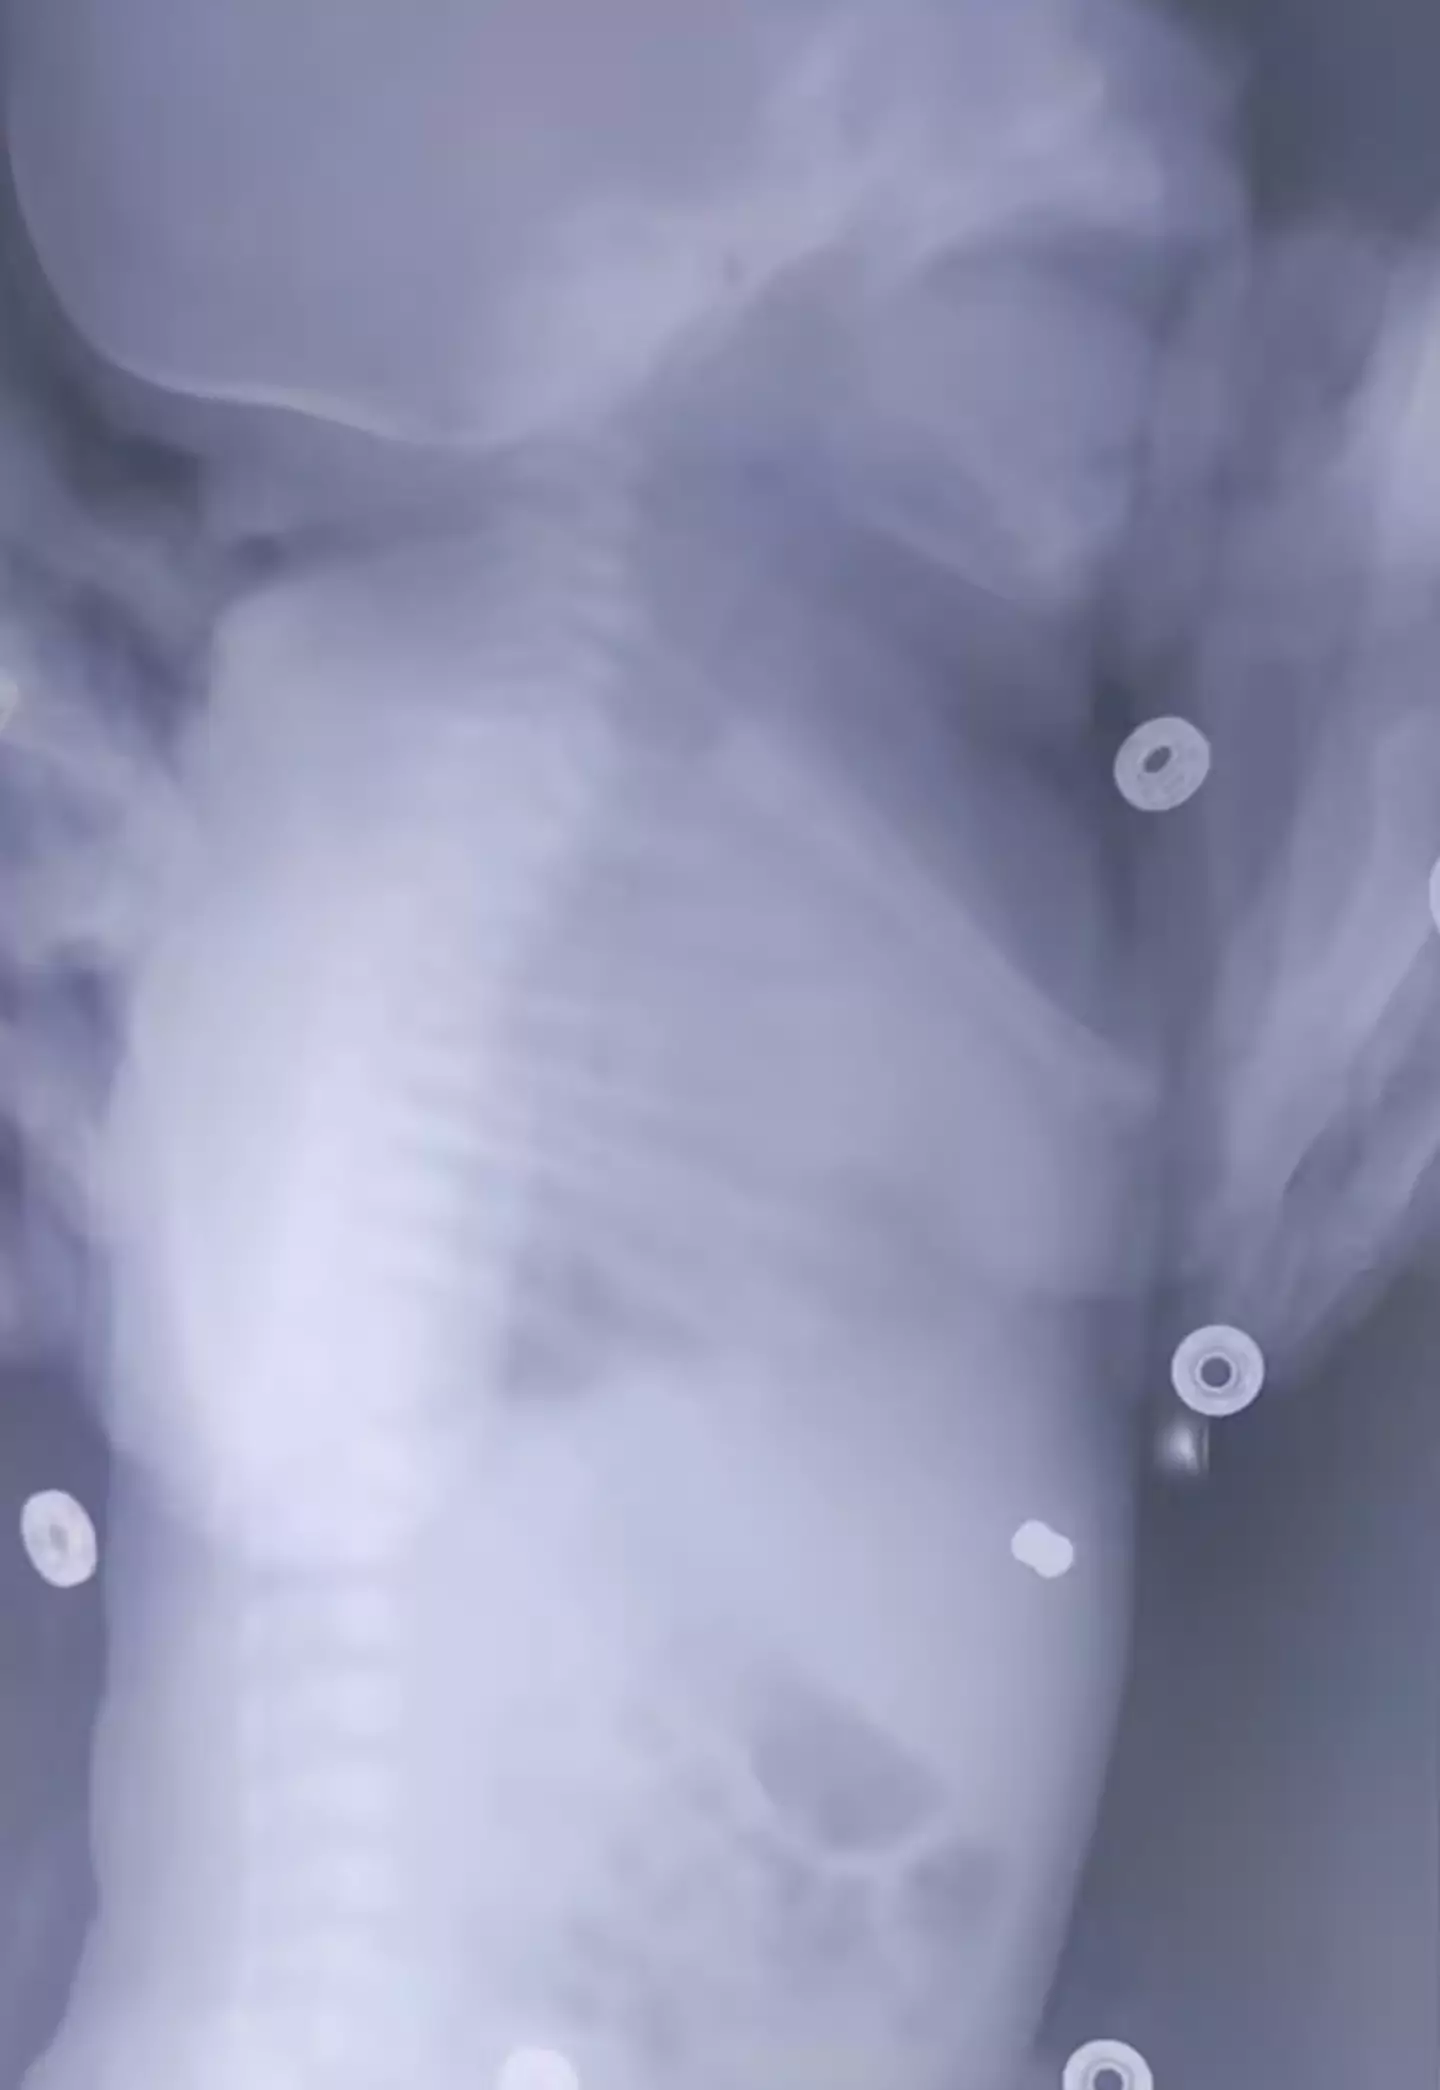

A baby was born with a rifle pellet lodged in her stomach after her mom was accidentally shot while pregnant with her.

The projectile was just under a centimetre long and around half a centimetre wide and didn't do any damage to the child's vital organs.

Once the child arrived, doctors were able to remove the air rifle pellet from underneath the child's skin in the stomach, before stitching up the baby.

The State Budgetary Institution of Healthcare of the Moscow Region said: "At the Moscow Regional Centre for Maternal and Child Health, neonatal surgeons removed a pellet from a pneumatic weapon from the anterior abdominal wall of a newborn baby.

"The neonatal surgery department (headed by Mikhail Georgievich Rekhviashvili, PhD) received a call about transferring a child with a foreign object - a pellet in the anterior abdominal wall.

"The newborn girl was delivered in satisfactory condition."